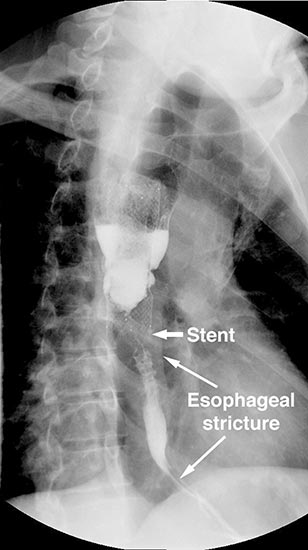

Figure 4. Postoperative barium swallow demonstrating free flow through the anastomosis with no residual stricture.

The patient had an uncomplicated course. His nasogastric tube was removed on postoperative day five. A water-soluble esophageal swallow study on postoperative day six demonstrated normal flow of contrast through the anastomosis and stomach into the jejunum, with no evidence of leak or obstruction (Figure 4). The patient was discharged to home on regular diet on postoperative day eleven. Pathologic analysis of the specimen revealed multiple strictures within the esophagus, to a diameter as narrow as 5 mm, and no evidence of malignancy. The patient had complete resolution of his dysphagia on 9 month follow-up and was returning to his baseline weight.